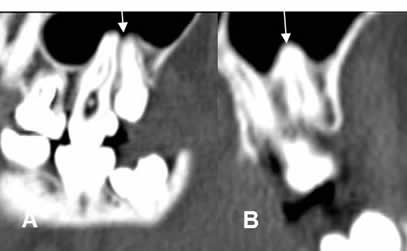

Fig 38. Enfermedad endodental.

A: TAC axial, B: TAC reconstrucción coronal y C: TAC reconstrucción sagital.

Reemplazo de la pulpa de los dientes, por caries extendidas internamente. (Flechas gruesas). Se encuentra perilucencia periapical, por enfermedad endodental.(Flechas delgadas).